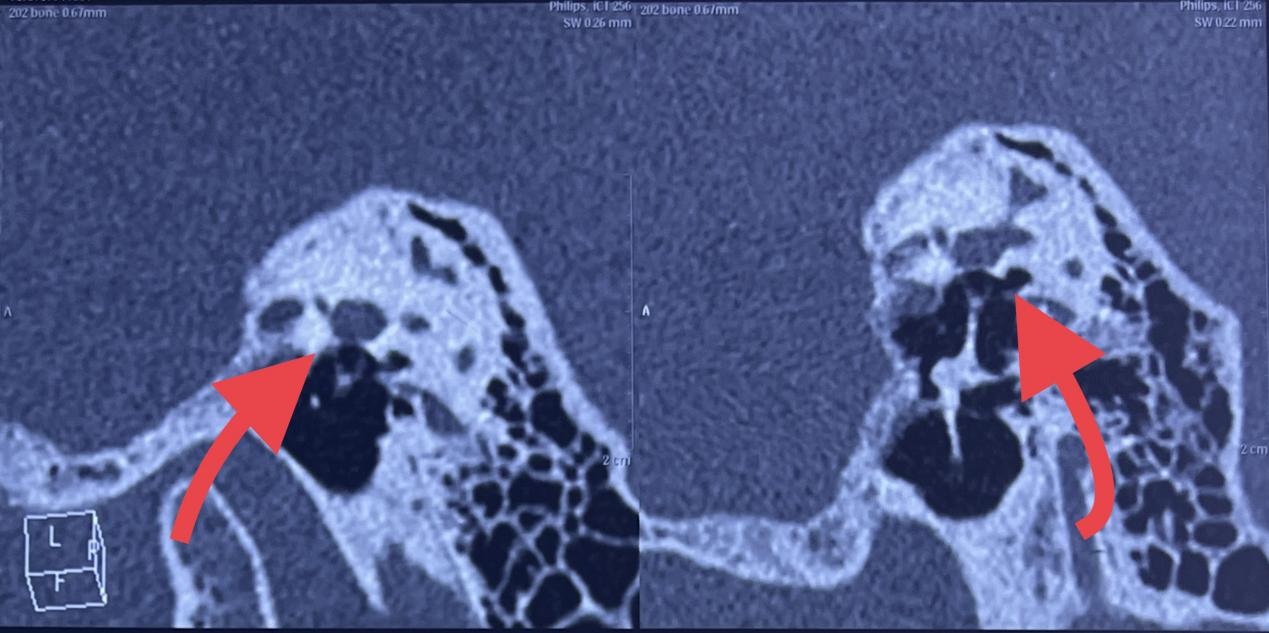

耳硬化症是一种特发于内耳骨迷路的骨代谢疾病,临床表现为传导性聋,进展后可累及耳蜗,发展为混合性聋。手术是耳硬化症的首选治疗方法。传统三棱针手动钻孔容易出现底板浮动、骨折、下沉等并发症,CO2激光通过高能量密度,可做到精确定位、创伤小等效果,明显减少术后并发症。

镫骨固定